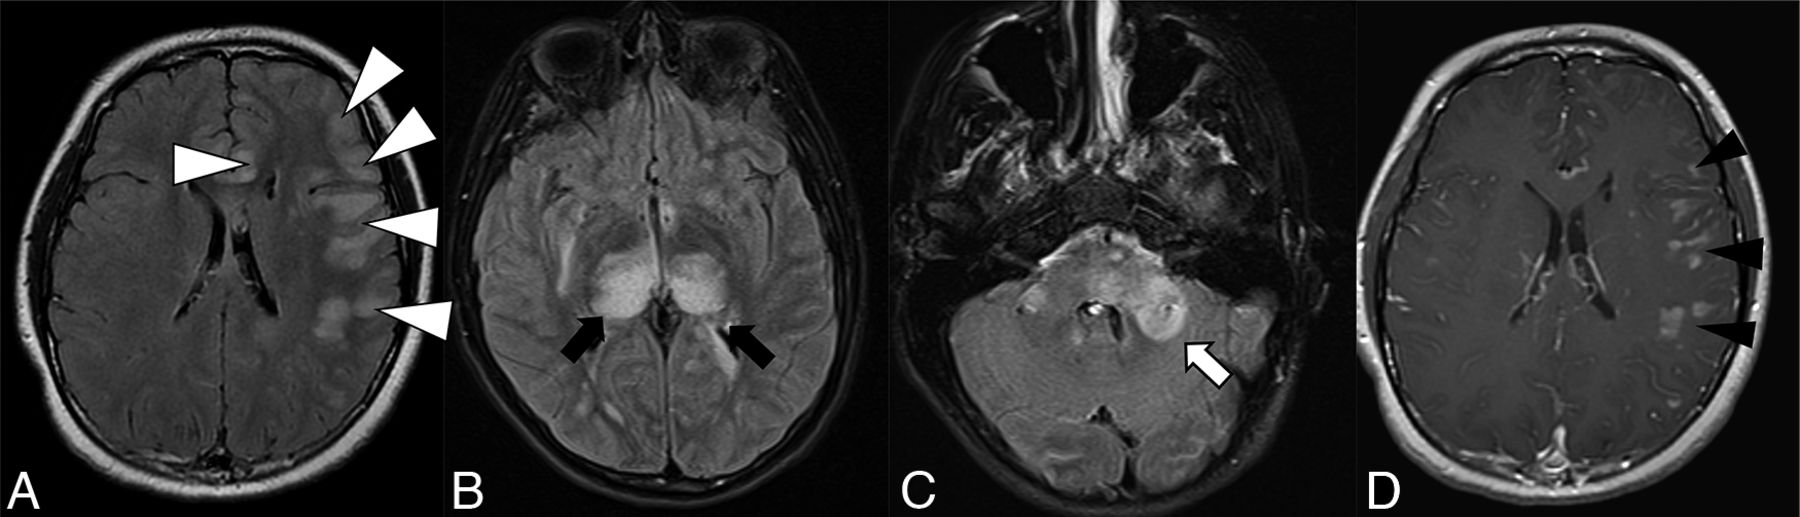

The overall imaging pattern was characterized as ADEM-like, optic neuritis (ON), myelitis (any cord signal abnormality), FLAIR-hyperintense lesions in anti-MOG-associated encephalitis with seizures (FLAMES), or any combination of the above. ADEM-like pattern was defined as multifocal supratentorial or infratentorial white or gray matter T2/T2-FLAIR hyperintense lesions with or without enhancement (Fig 1). When FLAMES occurred in combination with other patterns (ADEM-like, ON, or myelitis), the overall pattern was assigned as FLAMES (Fig 2).

Thirteen-year-old adolescent boy who presented with encephalopathy after a viral prodrome, found to have papilledema and opening pressure >39, subsequently found to have serum positivity for anti-MOG antibody. Brain MR imaging demonstrates features of ADEM-like pattern of pediatric MOGAD. A-C, FLAIR hyperintensity involving the left frontal subcortical white matter with ill-defined borders and beginning confluence (white arrowheads), bilateral thalami (black arrows), pons and brachium pontis (white arrow). D, Solid nodular enhancement associated with the left frontal white matter lesions.